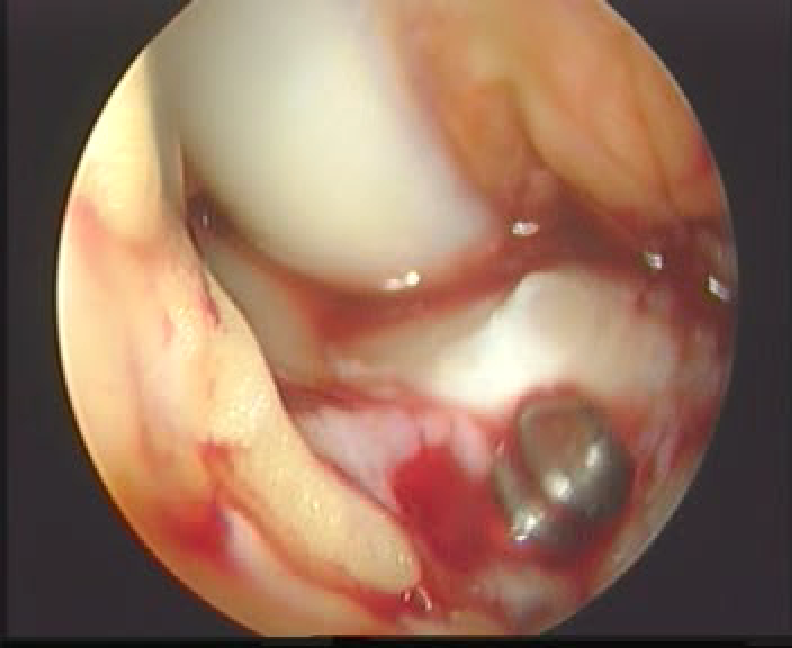

拉进移植物

界面螺钉固定移植物

上胫骨端界面螺钉

拉紧B-P-B,并行后抽屉试验,紧张重建韧带,上胫骨端的界面螺钉,必要时可用门型钉或普通螺丝钉加强固定。

用探钩检查,重建韧带张力良好,前抽屉试验阴性,膝关节屈伸正常。